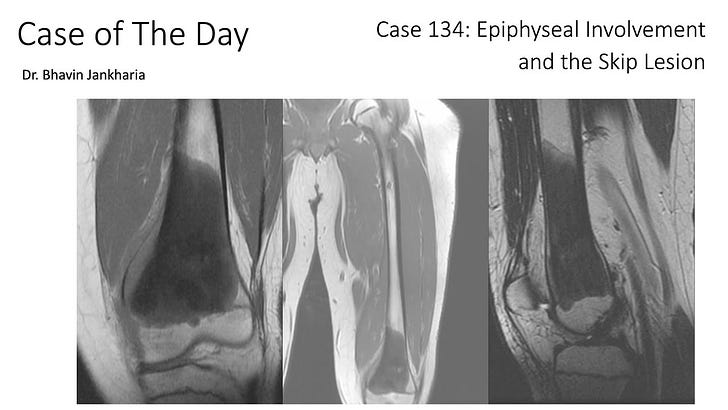

COD 134 - Epiphyseal Involvement and The Skip Lesion